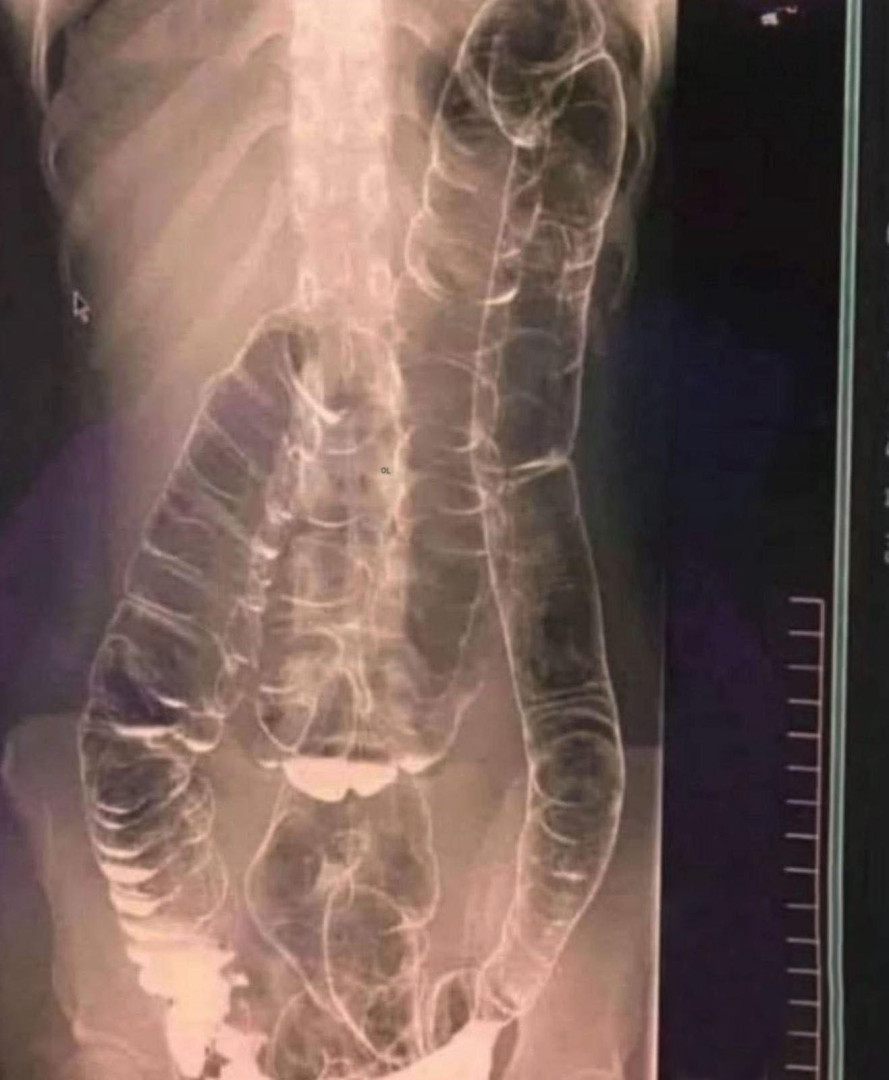

To właśnie przydarzyło się młodej kobiecie, której przypadek ujawniło imponujące zdjęcie rentgenowskie, wywołując dreszcze. Po ponad dwóch tygodniach bez wypróżnień zgłosiła się na konsultację. Rezultat: okrężnica tak rozszerzona, że sięgała aż do klatki piersiowej. Wszystko to jest spowodowane nagromadzeniem się starych, twardych stolców.